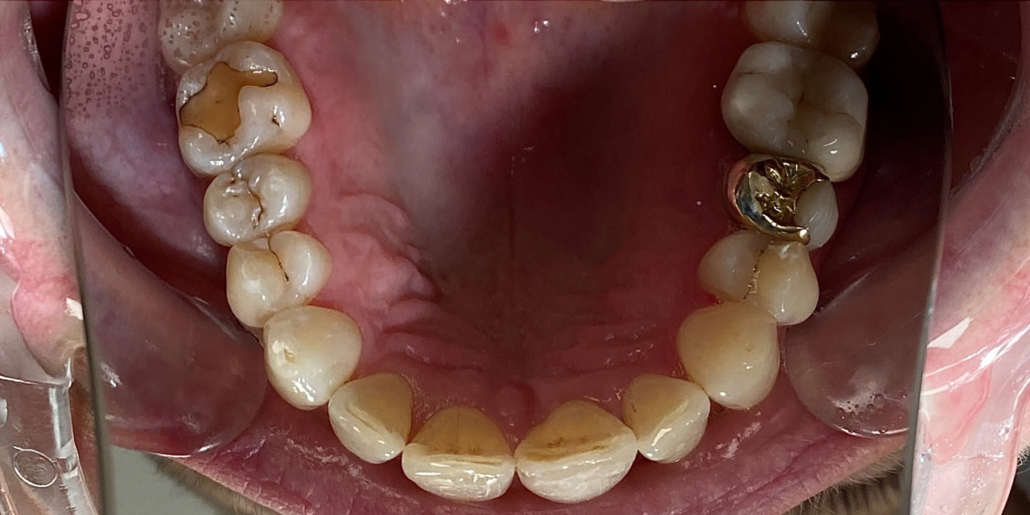

Zahnschienen sind äußerst vielseitige Hilfsmittel der Zahnmedizin – und können so verschiedene Beeinträchtigungen verbessern. In unserer Praxis in Essen setzen wir Zahnschienen in erster Linie ein, um Zahnfehlstellungen verschiedener Art zu behandeln. Hierzu gehören beispielsweise Zahnlücken, Engstände oder Bissprobleme (offener Biss/Kreuzbiss).

Unsere Praxis ist eine erfahrene Anlaufstelle für Zahnschienen in Essen und unterstützt Ihre Zahn- und Mundgesundheit mit modernen Technologien und individuellen Behandlungsplänen. Ein besonderer Vorteil unserer Zahnschienen ist, dass sich auch komplexere Fehlstellungen oder Schiefstände an Seiten- oder Backenzähnen korrigieren lassen.

Zunächst vereinbaren Sie einen kostenlosen Termin in unserer Zahnarztpraxis. Hier wird ein 3D-Scan Ihrer Zähne erstellt, sodass wir die Schwere der Fehlstellung einschätzen können. Dank einer Computersimulation können wir Ihren die voraussichtliche Veränderung Ihrer Zähne im Laufe der Behandlung bis zum endgültigen Ergebnis zeigen. Wir erstellen Ihren Behandlungsplan und kalkulieren ebenso Ihren Kostenplan. Ihre Schienen werden im Anschluss individuell für Sie hergestellt: Während der Behandlungsdauer erhalten Sie alle zwei Wochen eine neue Schiene, die für jeweils 22 Stunden am Tag getragen wird. Mit jeder neuen Schiene werden die Zähne etwas weiter in die Zielposition bewegt. Für die Zahnpflege sowie für die Mahlzeiten kann die Schiene unkompliziert herausgenommen werden. Gereinigt werden die Zähne wie gewohnt mit Zahnbürste und Zahnpasta. Ist das gewünschte Ergebnis erreicht, wird ein sogenannter Retainer eingesetzt, der die Zähne dauerhaft in Form hält. Häufig handelt es sich um einen dünnen Draht an der Innenseite der Zähne oder eine transparente Schiene, die nur nachts getragen wird.

Unsere Praxis ist Ihr Ansprechpartner für Zahnschienen in Essen. Anders als bei reinen Online-Anbietern, profitieren Sie bei uns durch eine umfangreiche Betreuung während Ihrer gesamten Behandlungsdauer und darüber hinaus. Auch komplizierte Fehlstellungen können wir beheben – bei reinen Online-Anbietern lassen sich nur leichte bis mittelschwere Fehlstellungen im Frontzahnbereich, also den sogenannten „Social Six“ (Zähne 3-3) korrigieren. Bei uns, der Zahnarztpraxis Dr. Woeckner, sind wir bemüht, Ihre Termine schnell zu erledigen und lange Wartezeiten zu Vermeiden. Den Großteil Ihrer Behandlung macht aber natürlich das regelmäßige Tragen der Schienen zuhause aus. Wie lang die Behandlungsdauer ist, hängt unter anderem davon ab, wie schwer die zu korrigierende Fehlstellung ist. In der Regel dauert die Therapie zwischen drei und zwölf Monaten. Der Kostenpunkt hängt vom Schweregrad und der damit zusammenhängenden Behandlungsdauer ab. Meist bewegen sich die Kosten zwischen 2000€ und 4000€.